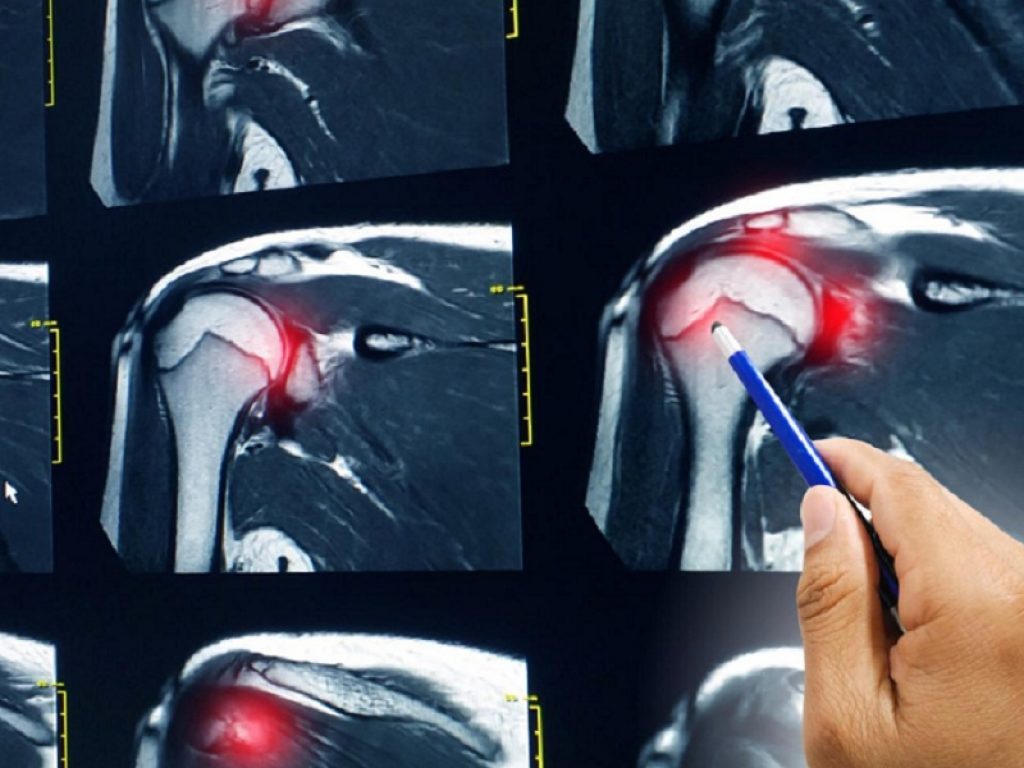

Riparazione artroscopica della cuffia dei rotatori: l’uso di una terapia cocktail con farmaci antidolorifici postoperatori ha mostrato benefici sul dolore

Nei pazienti sottoposti a riparazione artroscopica della cuffia dei rotatori, l’uso di una terapia cocktail con farmaci antidolorifici postoperatori ha mostrato benefici sul dolore. E’ quanto evidenziano i risultati di uno studio pubblicato su Journal of Shoulder and Elbow Surgery.

Takeshi Teratani, dell’Ouryouji Orthopaedic Hospital in Giappone, ha analizzato l’efficacia della terapia a base di un cocktail di antidolorifici dopo la riparazione artroscopica della cuffia dei rotatori (ARCR).